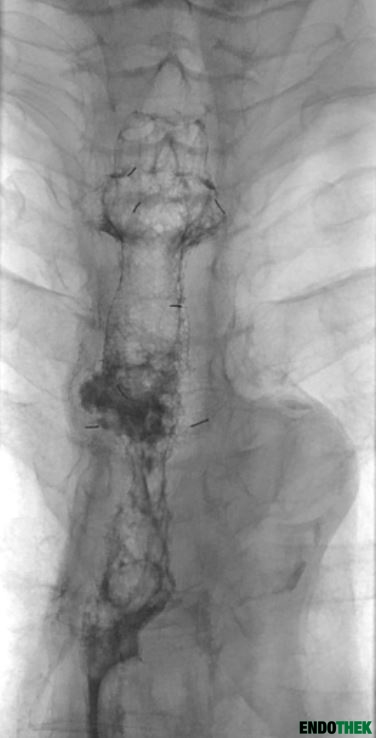

Ösophagusstenose bei Anastomosenstenose nach Ösophagusresektion bei Plattenepithelkarzinom und multiplen Stentimplantationen

St. p. Ösophagusresektion bei Plattenepithelkarzinom und multiplen Stentimplantationen in der Vorgeschichte